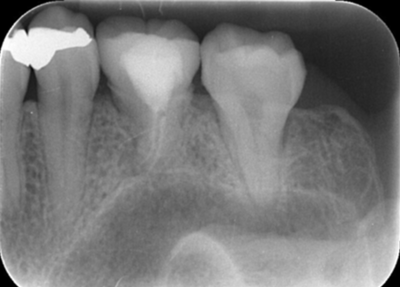

移植手術3ヶ月後のレントゲン画像

移植3ヶ月後。

歯根周囲に透過像を認めるが動揺などはなく、歯周ポケットも形成されていなかった。

移植12ヶ月後のレントゲン

移植12ヶ月後。セラミッククラウンで歯冠を修復した。

デンタルX線写真では透過像もほぼ消失している。